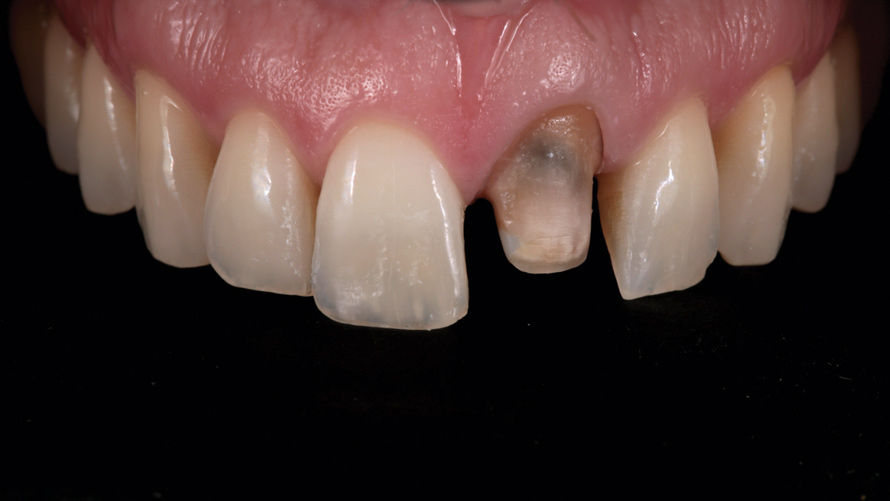

(6.) Case 2: Discolored stump immediately following sectioning and removal of the existing ceramic restoration.

Figure 6

The prosthetic and endodontic protocols were nearly identical for all phases of treatment in both cases. At the first operative visit, the existing ceramic crown was carefully sectioned and removed (Figure 5 and Figure 6). This was followed by the removal of any existing supragingival core materials in the first case. Next, the highly chromatic underlying natural stump shade was recorded, and a provisional restoration was fabricated and luted with temporary cement. Each patient was then immediately dismissed to the endodontist for same-day elective root canal therapy and internal bleaching treatment with the walking bleach technique.